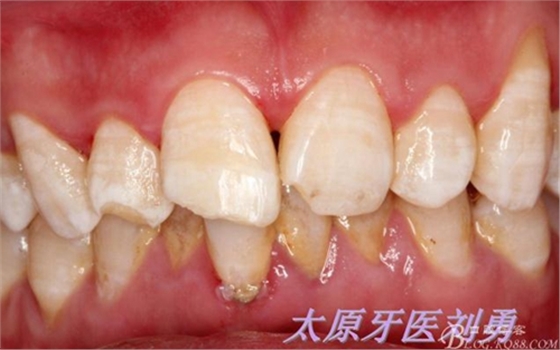

最后附一例樹(shù)脂關(guān)閉牙間隙的病例。具體操作不做詳細(xì)描述。

術(shù)前如下: